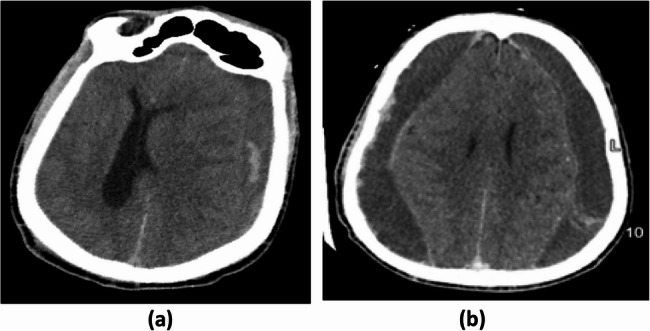

Results: Forty-eight patients were included, with a median age of 38 years. The majority (52.1%) had a CD4 count ≥ 200 cells/µL. Males comprised 50% of the cohort, with a higher proportion of males in the CD4 count ≥ 200 group (p = 0.029). The median admission Glasgow Coma Scale (GCS) was 14. Common clinical presentations included headaches (47.9%) and hemiparesis (43.8%). ART coverage was 58.3%, and bilateral CSDH was diagnosed in 25%. Most patients (72.9%) received two burr holes. Postoperative complications included recurrence (16.7%), septicemia (10.4%), and subdural empyema (2.1%). Mortality rate was 14.6%. Factors significantly associated with mortality included low GCS, INR > 1.2 and septicemia.

Conclusions: CSDH in HIV-infected individuals presents at a younger age than in the general population. While most patients had CD4 count of ≥ 200 cells/µL, CD4 level was not a predictor of surgical outcome. Mortality was associated with low GCS, increased INR, and septicemia.